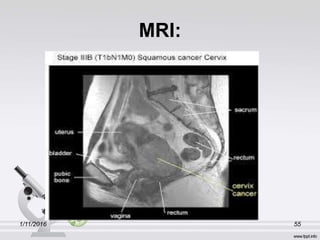

MRI:

1/11/2016 55

1/11/2016 56